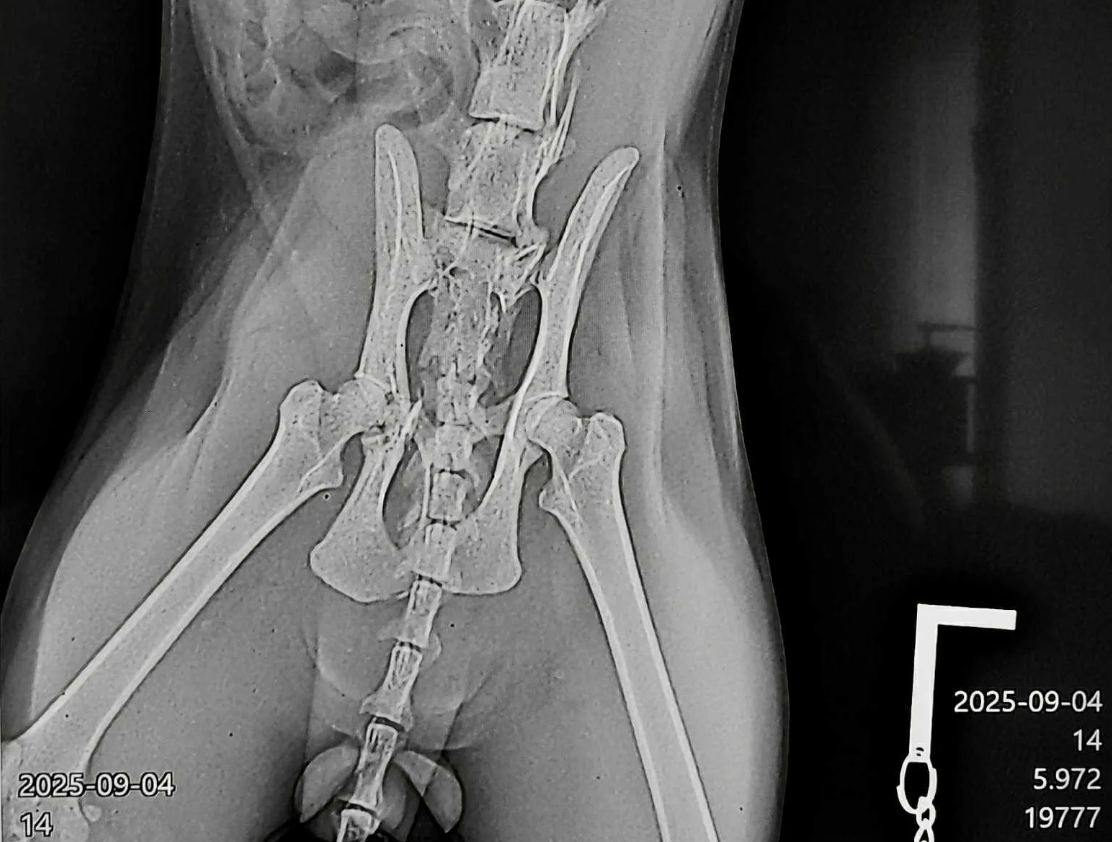

Котаракът е със сериозни травми и в момента е хоспитализиран и на обезболяващи.

Необходима е спешна операция на стойност около 1000 лева, както и човек, който да се грижи за него в домашни условия за период от около два месеца, докато се възстанови.